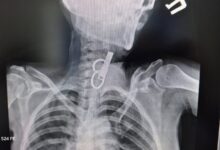

Стан новонародженої дівчинки, яку залишили в під’їзді багатоповерхівки у Тернополі, поступово стабілізується.

Наразі дитина перебуває під наглядом лікарів обласної дитячої клінічної лікарні.

“Стан вже трошки покращився, але ще важкий. Вже зняли інкубацію, є позитивна динаміка”, – наголосив Володимир Семерез.